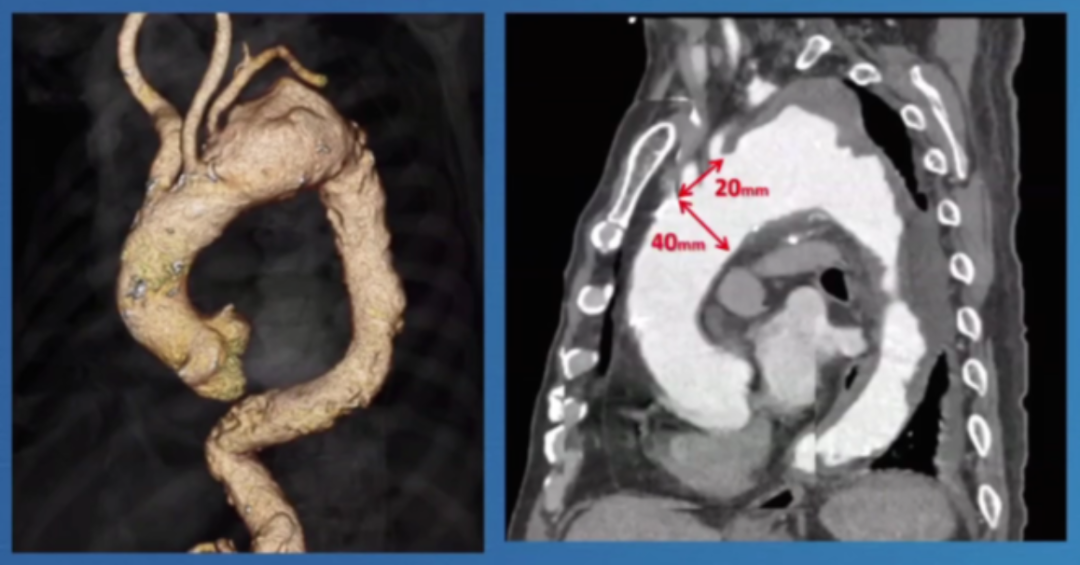

研究表明逆⾏A型夹层的发生率较高,除了其近端锚定区选择不当会增加⻛险外,对于亚洲患者解剖特点也会有一定的风险,入⼸部直径超过40mm时,伴有⾎栓时⼿术难度增加;中国患者更年轻,夹层常延伸⾄左颈总动脉起始部。现有器械在亚洲患者中常⾯临锚定区不⾜的问题。

此外,报告强调了健康主动脉的重要性,升主动脉直径<38mm是关键标准。曾有案例显示,在40mm主动脉植入支架后发生灾难性逆行A型夹层,这警示临床医生必须在健康主动脉段锚定,避免在夹层病理区域进行操作。